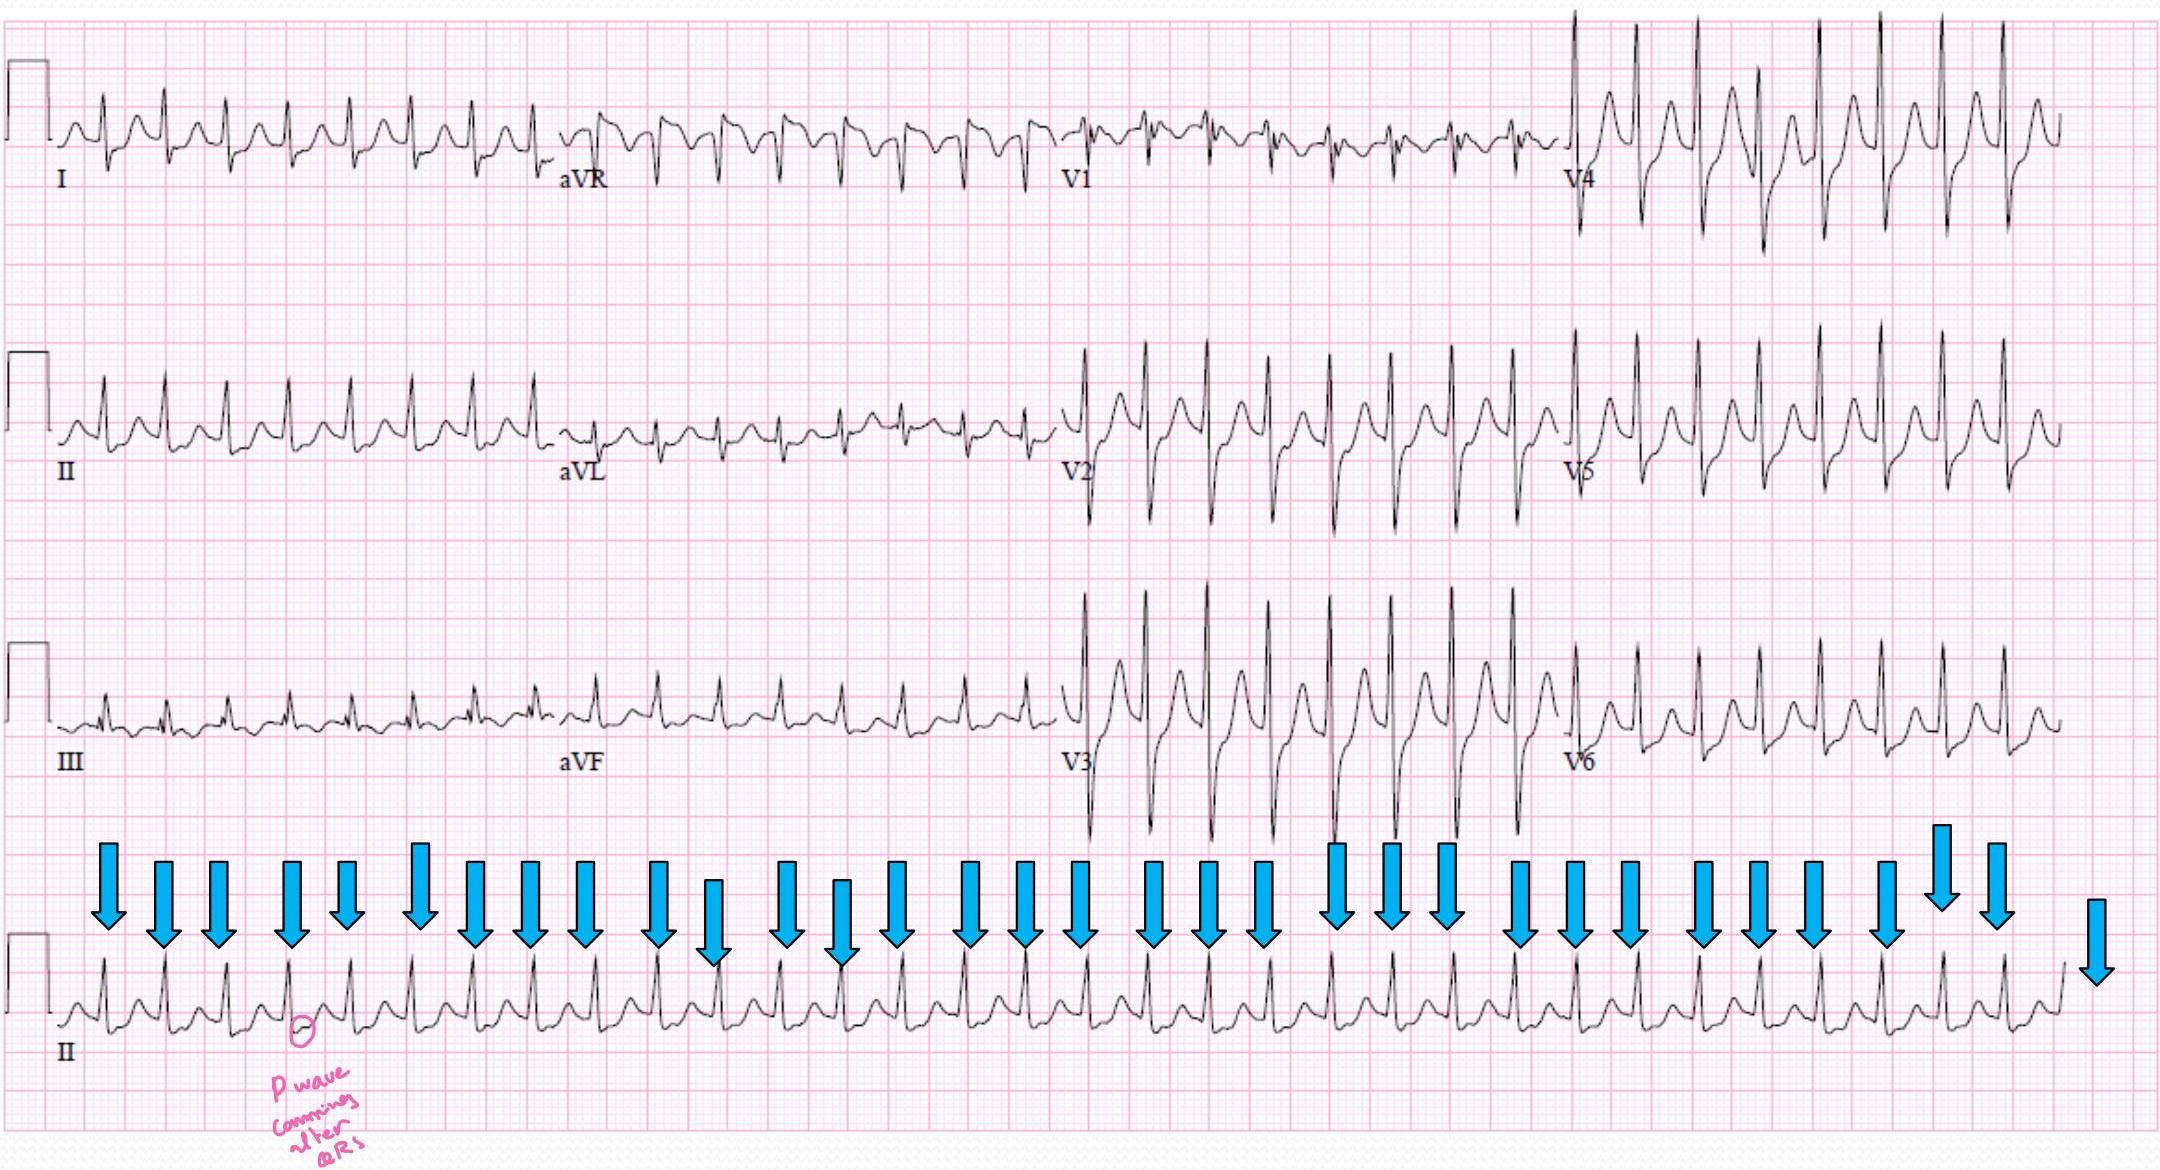

Paroxysmal Supraventricular Tachycardia (SVT)

(AV nodal reentrant tachycardia)

(Paroxismal SVT / AVNRT):

| Heart Rate | Rhythm | P Wave | PR interval (in seconds) | QRS (in seconds) |

|---|---|---|---|---|

| 140-250 bpm | Regular | Abnormal P before each QRS (difficult to see) | <.20 | <.12 |

TABLE 2. Clinical Signs and Symptoms Associated With Sinus Tachycardia and SVT

| Sinus Tachycardia | SVT | |

|---|---|---|

| Heart rate (bpm) | Infants, below 220 Children, below 180 | Infants, above 220 Children, above 180 |

| Beat-to-beat interval | Variable | Fixed |

| P waves | Visible; normal axis | Not visible or abnormal axis Usually hidden in QRS or ST segment |

| Onset | Gradual | Abrupt |

| Termination | Gradual | Abrupt |

| Response to vagal maneuvers | Rate slows gradually, then returns | Tachycardia terminates abruptly (if successful) |

| Response to cardioversion | No conversion | Conversion |

| Fever | Strongly suspected when fever is present | 2%-3% of patients have fever on presentation |

| Presentation with shock | Possible | Possible |